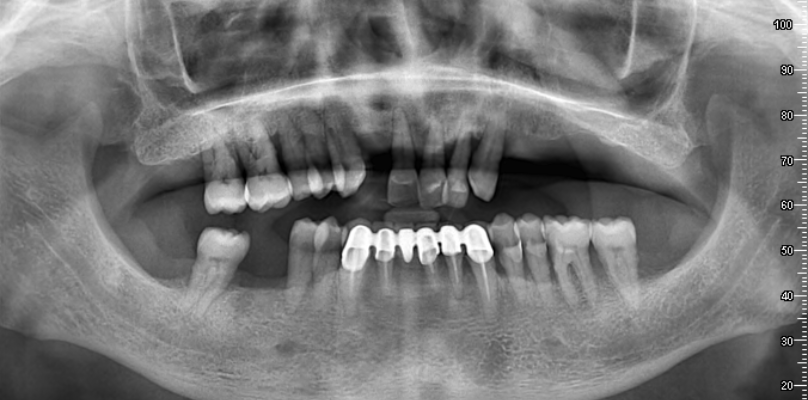

La première étape du processus de traitement consiste à prendre des images radiographiques détaillées. Ces images aident à déterminer le plan de traitement le plus approprié en évaluant la structure de votre mâchoire et votre santé dentaire. Nos radiographies révèlent à quel point le processus de traitement est extrêmement minutieux.